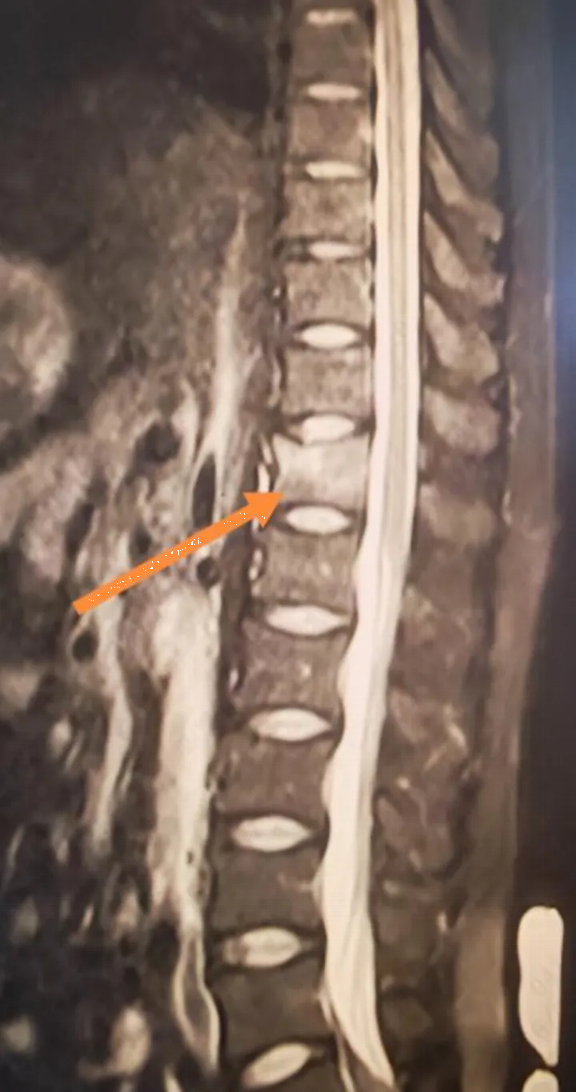

Kết quả chụp MRI khiến anh hoàn toàn sững sờ: gãy xẹp đốt sống T12.